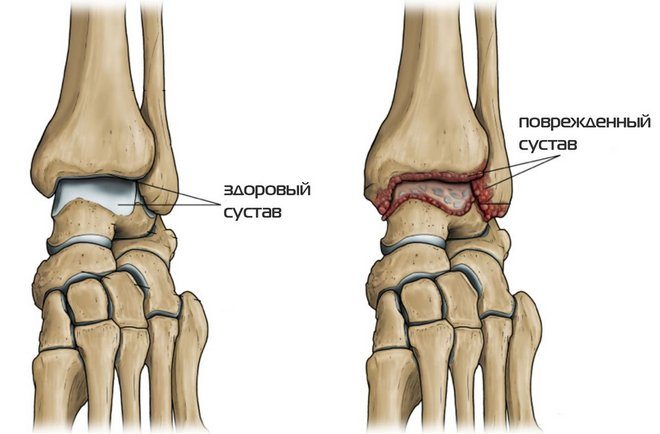

Артритом голеностопного сустава называется воспалительно-деструктивная патология, поражающая костные и хрящевые структуры. По мере прогрессирования заболевания повреждаются мышцы, связки, сухожилия, чувствительные нервные окончания.

Термин «артрит» объединяет обширную группу воспалительных поражений голеностопного сустава, провоцирующих его деформацию. От происхождения патологии, формы ее течения зависит терапевтическая тактика. Артриты голеностопа классифицируются следующим образом: